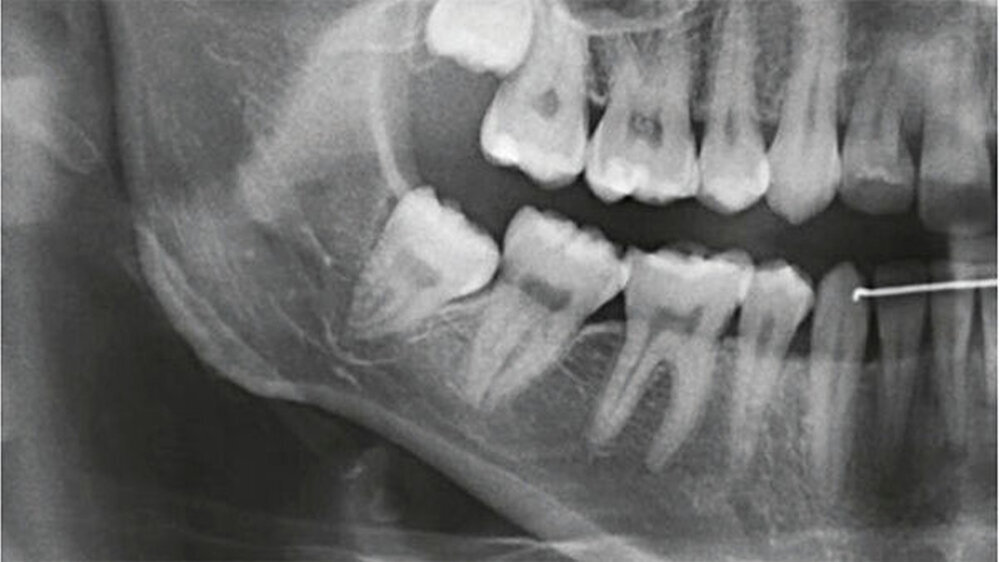

Bei der 27-jährigen, gesunden Patientin, kam es zu rezidivierender Perikoronitis des teilretinierten Zahns 48 (Abb. 1a). Primär wurde eine OPT-Aufnahme zur Operationsplanung erstellt (Abb. 1b). Dabei zeigte sich eine komplette Überlagerung der Zahnwurzel über den C. mandibulae. Zur weiteren Abklärung der Lagebeziehung wurde eine DVT-Aufnahme erstellt (Abb. 1c). Eine linguale Lage des C. mandibulae zur Zahnwurzel konnte festgestellt werden. Eine knöcherne Begrenzung des C. mandibulae zur Zahnwurzel fehlte.